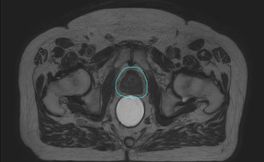

Am 19.6.2018 wurden in Tübingen die ersten Patienten am Unity System mit dem 1.5 T MRT untersucht und die ersten MR-basierten Bestrahlungspläne berechnet. Die ersten Untersuchungen erfolgten bei Patienten mit Prostata- und Darmkrebs. Die ersten Behandlungen mit dem MR-geführten Linac werden nach der intensiven Schulungsphase erfolgen.

Patient mit Prostatakrebs, T2w 3D TSE MRI, 19.06.18, Elekta Unity

Neue Methode zur Strahlentherapie des Prostatakarzinoms in Tübingen ausgezeichnet

Oberarzt PD Dr. Arndt-Christian Müller aus der Universitätsklinik für Radioonkologie und sein Team haben für die ersten Ergebnisse zur MR-basierten bildgestützten Strahlentherapie des Prostatakarzinoms den Posterpreis auf dem Forschungskolloquium der Medizinischen Fakultät 2018 erhalten. In dieser Studie werden im Verlauf der Hormon- und Strahlentherapie wiederholt MRT-Untersuchungen durchgeführt. Diese Untersuchungen erlauben es, die Strahlentherapie auf Veränderungen der Prostata während der Therapie anzupassen und somit eine optimale Schonung der Harnröhre und es Enddarms sowie der Harnblase zu ermöglichen. Die Studie wird durch die Medizinische Fakultät Tübingen unterstützt. Die MRT-Untersuchungen erfolgen in Kooperation mit der Abteilung für Diagnostische Radiologie.